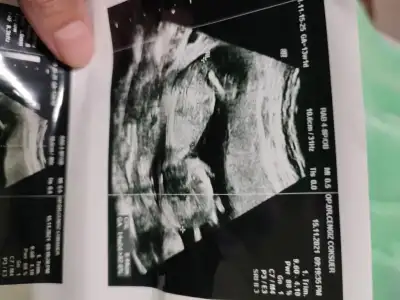

İkra Meyra, babada yorum yapabilir misin lütfen :) 9 hafka

• Screenshot_2021-11-12-16-06-09-449_com.miui.gallery.webp

Screenshot_2021-11-12-16-06-09-449_com.miui.gallery.webp

16,5 KB · Görüntüleme: 41

• IMG_20211112_143949.webp

IMG_20211112_143949.webp

35,2 KB · Görüntüleme: 40